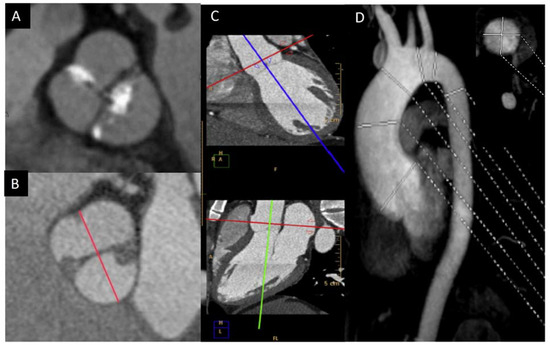

5. Aorta Involvement

- Although TTE is the technique of choice to identify valve morphotype, valve dysfunction, and ascending aorta dilation, CT and CMR improve the accuracy of aorta size measurement.

- A major benefit of CT is its superior spatial resolution, by which the aortic valve can be evaluated for morphology and calcification, ascending aorta size accuracy, and reproducibility measured and coronary arteries assessed.